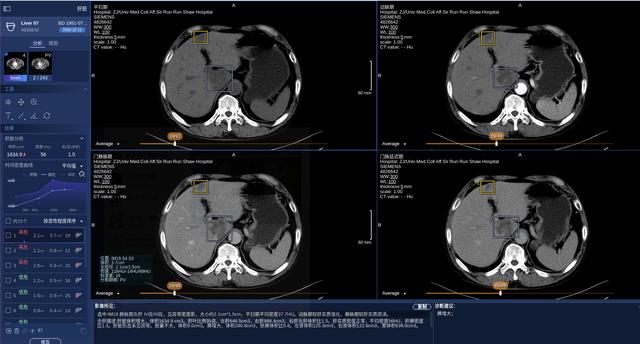

眼前的肝脏CT影像上 , 经过人工智能算法 , 自动显示了红色的高危病灶和绿色的低危病灶 , 并以蓝色和黄色方框框选出病灶所在的位置 , 一目了然 。 照片下方 , 影像所见的数据 , 已直接生成了一段文字 , 上面还有一个贴心的“复制”按钮 , 供医生阅片后放入病历 。文章插图

肝脏CT智能临床解决方案产品界面

“这个过程以前需要医生手动处理 , 一页页去翻 , 再进行比对分析 , 工作量很大 , 现在只需交给人工智能 , 就可以生成非常直观的扫描结果和三维手术方案规划 。 ”技术人员介绍 。